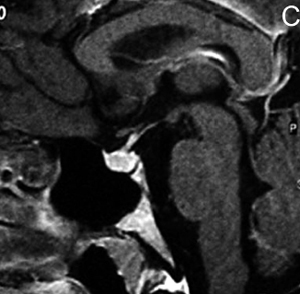

Figura 17A y B. Cortes coronal y axial transversal, T1w Gad. Macroadenoma con crecimiento hacia lateral (entre puntas de flecha), mayor a derecha con invasión de ambos senos cavernosos; el quiasma está libre.Los adenomas invasores (Figuras 18 y 19) constituyen un grupo aparte y de acuerdo con series recientes publicadas representan entre 10% a 35% de los adenomas pituitarios operados49. En estos casos el potencial de invasión es estimado con mayor precisión con estudios histoquímicos y ultraestructurales de las muestras obtenidas durante la cirugía. Estos estudios patológicos, en conjunto con la cuantía de tumor residual demostrada con las neuroimágenes postoperatorias, definirán la conducta terapéutica a seguir.

Figura 18A y B. Cortes sagitales, secuencia T1Gad. Macroadenoma invasor que se extiende al seno esfenoidal, al clivus, crece en el espacio retroselar, ocupa la cisterna supraselar y se extiende a la región subfrontal.

Figura 19A y B. Cortes sagitales T1w antes y después de inyección de Gadolinio. El tumor (prolactinoma) crece hacia caudal, invade el seno esfenoidal y erosiona el clivus (puntas de flecha), dejando libre la cisterna quiasmática. Los adenomas pituitarios invasores tienen características histológicas benignas, los malignos (carcinomas pituitarios) constituyen sólo el 0,2-0,5% de todos los tumores pituitarios50 y generalmente son macroadenomas funcionantes recidivados,que se presentan con metástasis subaracnoideas, cerebrales o sistémicas (Figuras 20 A, 20B, 20C y 20D).